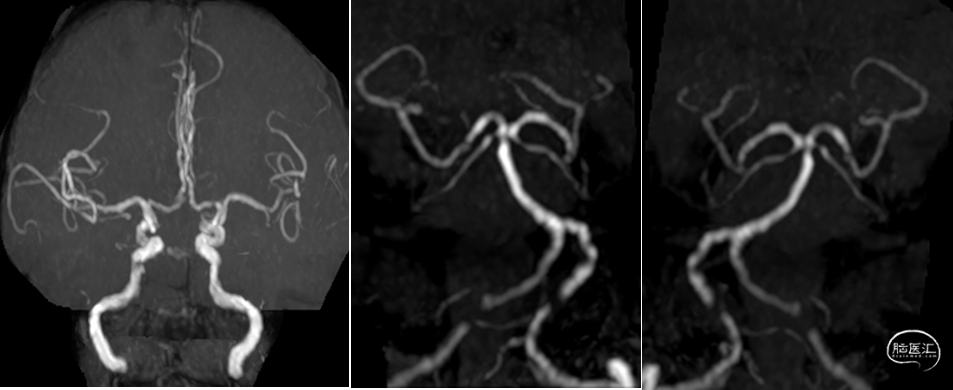

头颅核磁示:双侧小脑、双侧枕叶多发性脑梗死,部分趋于急性期。头颅磁共振MRA提示:双侧椎动脉V4重度狭窄;基底动脉上段轻度狭窄。

DSA提示:双侧颈内动脉及颅内血管未见明显狭窄,右侧椎动脉优势,左侧椎动脉纤细,V4段闭塞。右侧椎动脉起始处重度狭窄,右椎V4段及基底动脉近端局限性重度狭窄。患者反复间断发作头晕,考虑后循环缺血引起的TIA发作,且强化药物治疗效果不佳,有介入治疗适应症。